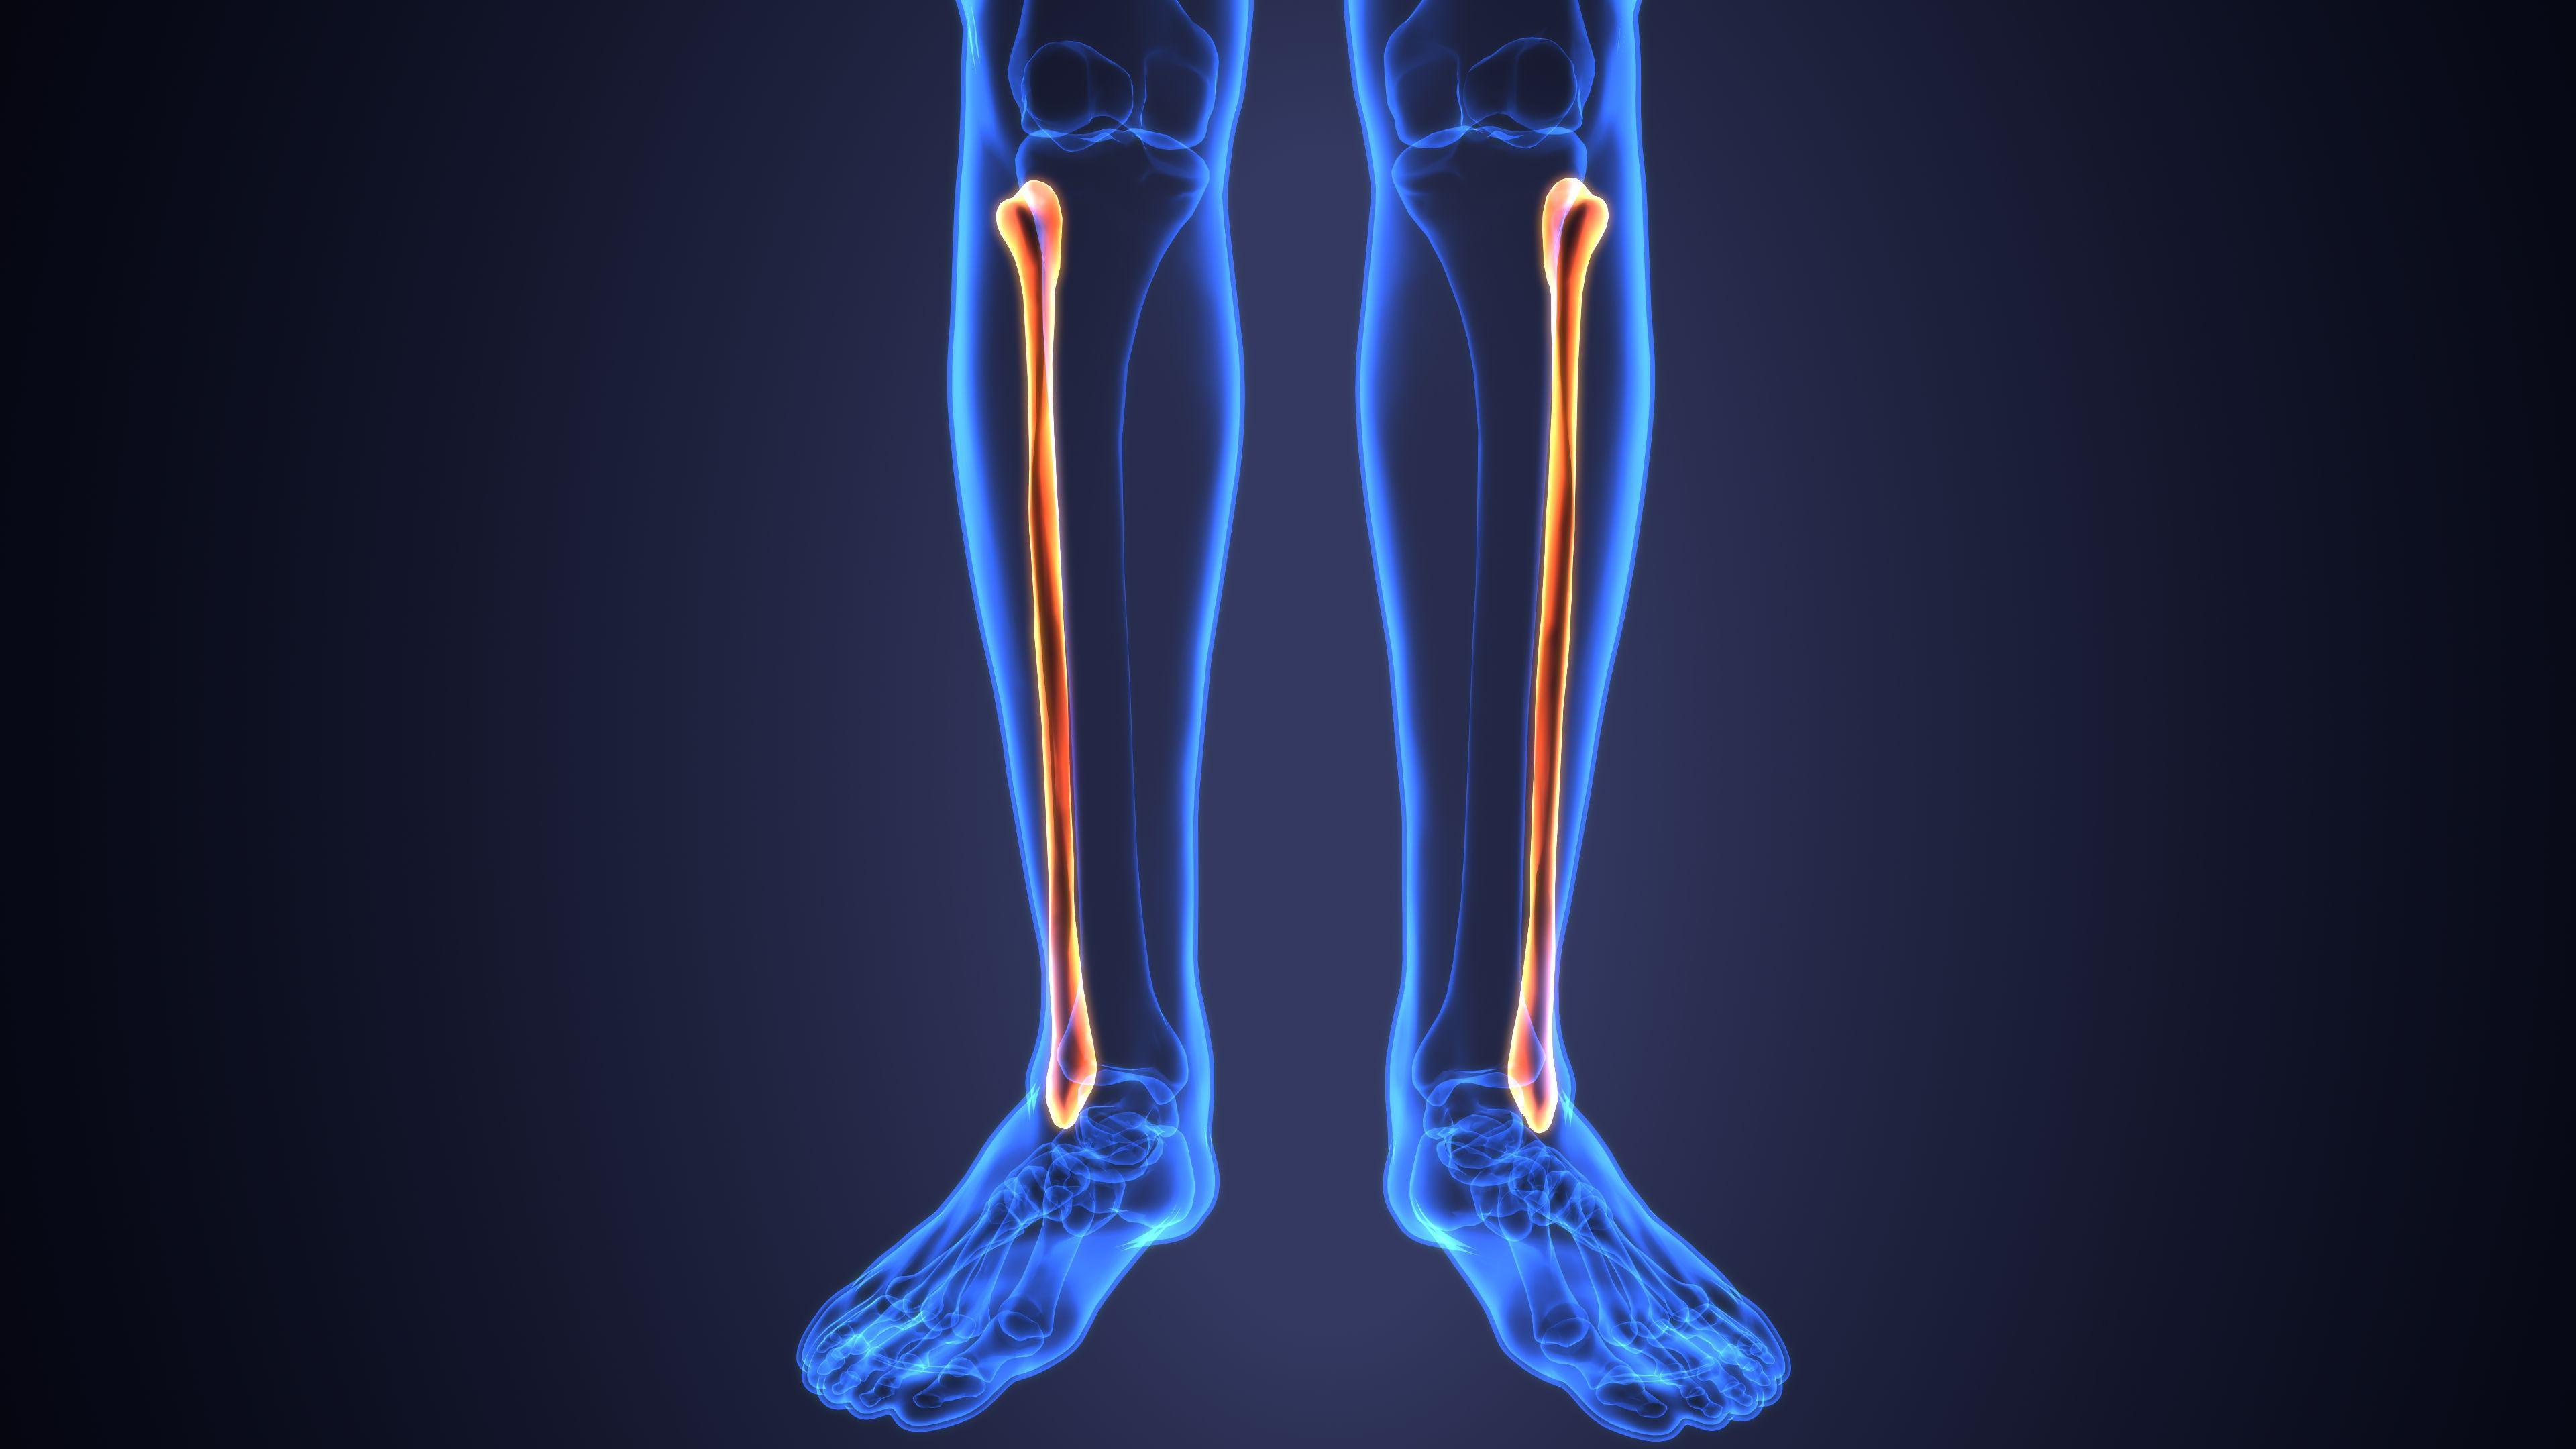

Анатомия фибулы: Подробные фотографии и схемы